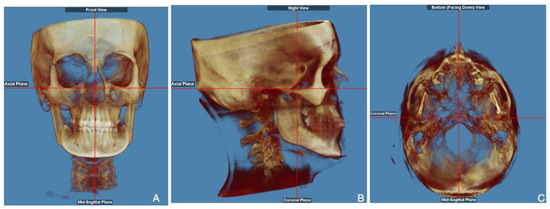

2. Materials and Methods

- Verma, S.K.; Maheshwari, S.; Gautam, S.N.; Prabhat, K.; Kumar, S. Natural head position: Key position for radiographic and photographic analysis and research of craniofacial complex. J. Oral Biol. Craniofac. Res. 2012, 2, 46–49. [Google Scholar] [CrossRef]

- Tian, K.; Li, Q.; Wang, X.; Liu, X.; Wang, X.; Li, Z. Reproducibility of natural head position in normal Chinese people. Am. J. Orthod. Dentofac. Orthop. 2015, 148, 503–510. [Google Scholar] [CrossRef]